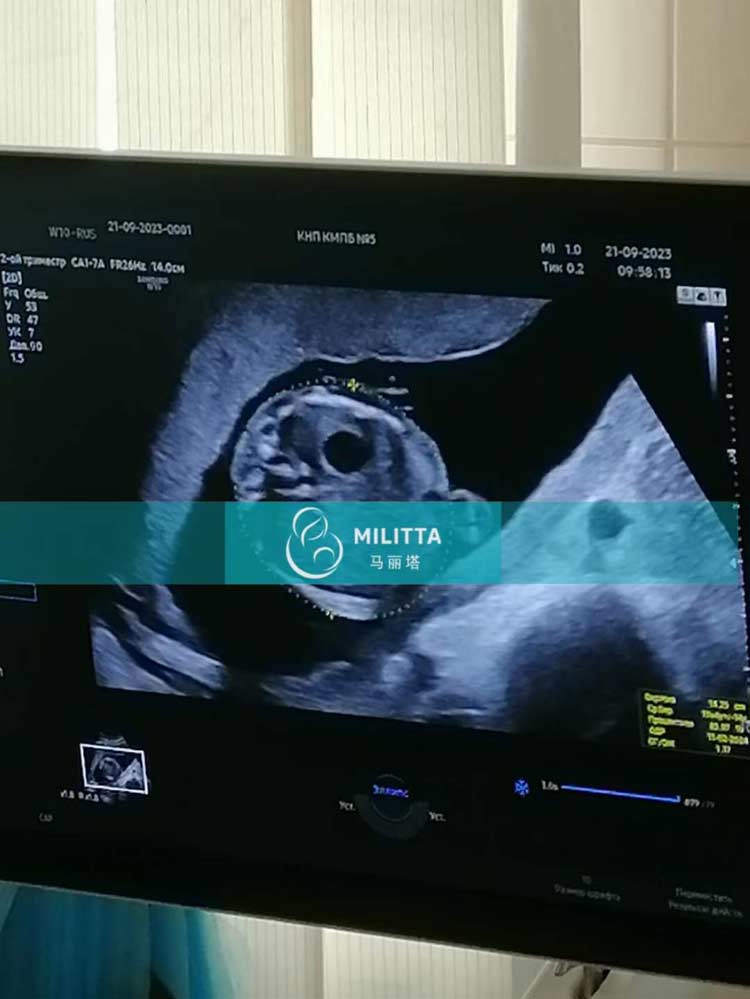

青海M夫妇的乌克兰试管来做孕19周的B超孕检,顺利通过检查

安排这位青海M夫妇的乌克兰试管来做孕19周的B超孕检,顺利通过了检查,胎儿又长大了不少